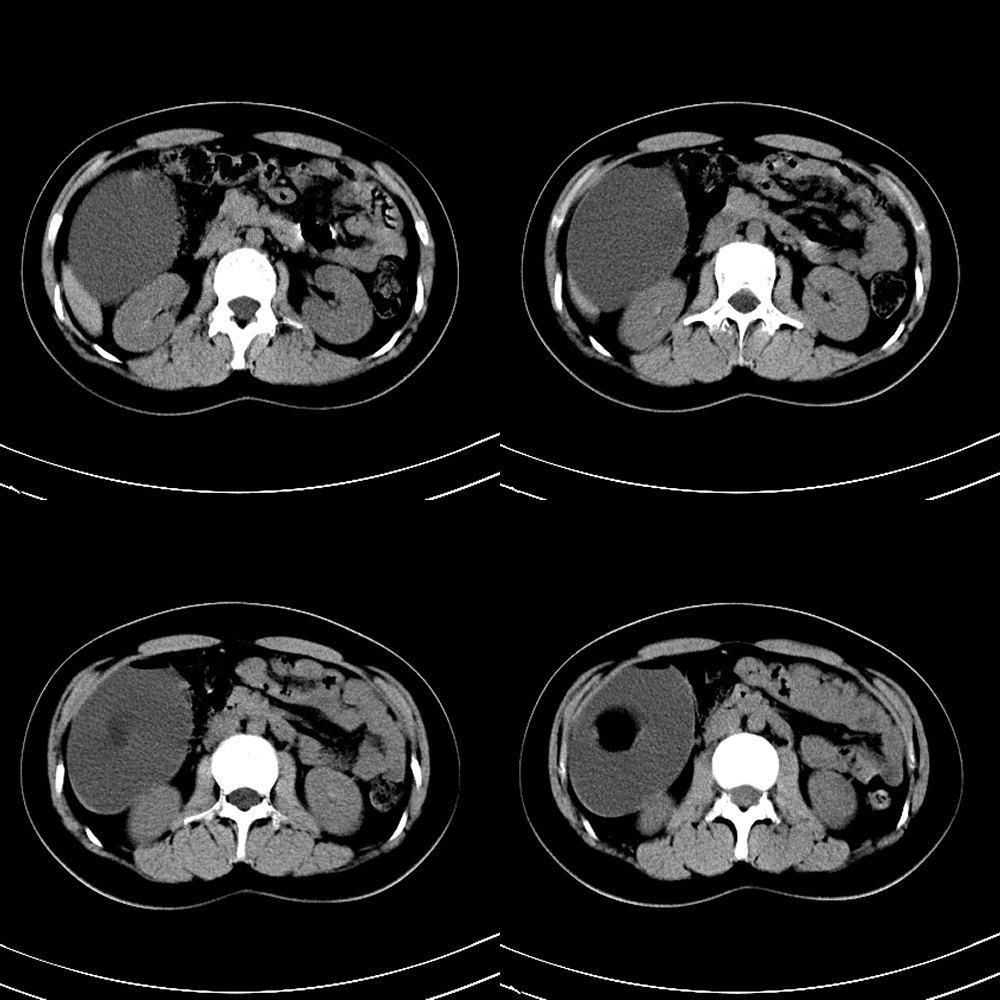

标题: CT13946:F18Y,一个典型病例。

f18y,无意中发现。无症状。典型病例,但是肿瘤定位在哪里?注:中心低密度ct值为-118hu.

注:中心低密度ct值为-118hu.